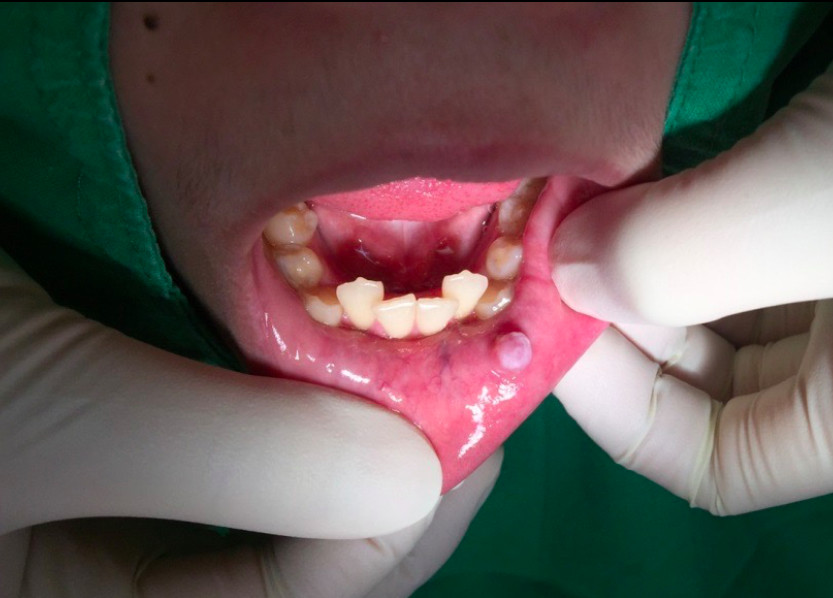

▲吃東西不小心咬到嘴唇,或是咀嚼時不小心傷到嘴邊肉,都可能產生「小唾液腺囊腫」(圖/記者李佳蓉攝)

林泰興解釋,小唾液腺囊腫主要會長在嘴唇、口腔、舌下。患部周圍的嘴唇、兩頰黏膜會出現無痛、大小起伏不定,感覺會動,質地偏軟的淡藍色或半透明圓形小水泡。通常只會有單顆,直徑大約0.2-1cm左右,不會太嚴重的症狀,但也有傷口感染的風險。

▲小唾液腺囊腫主要會長在嘴唇、口腔、舌下。(圖/ETtoday資料照)